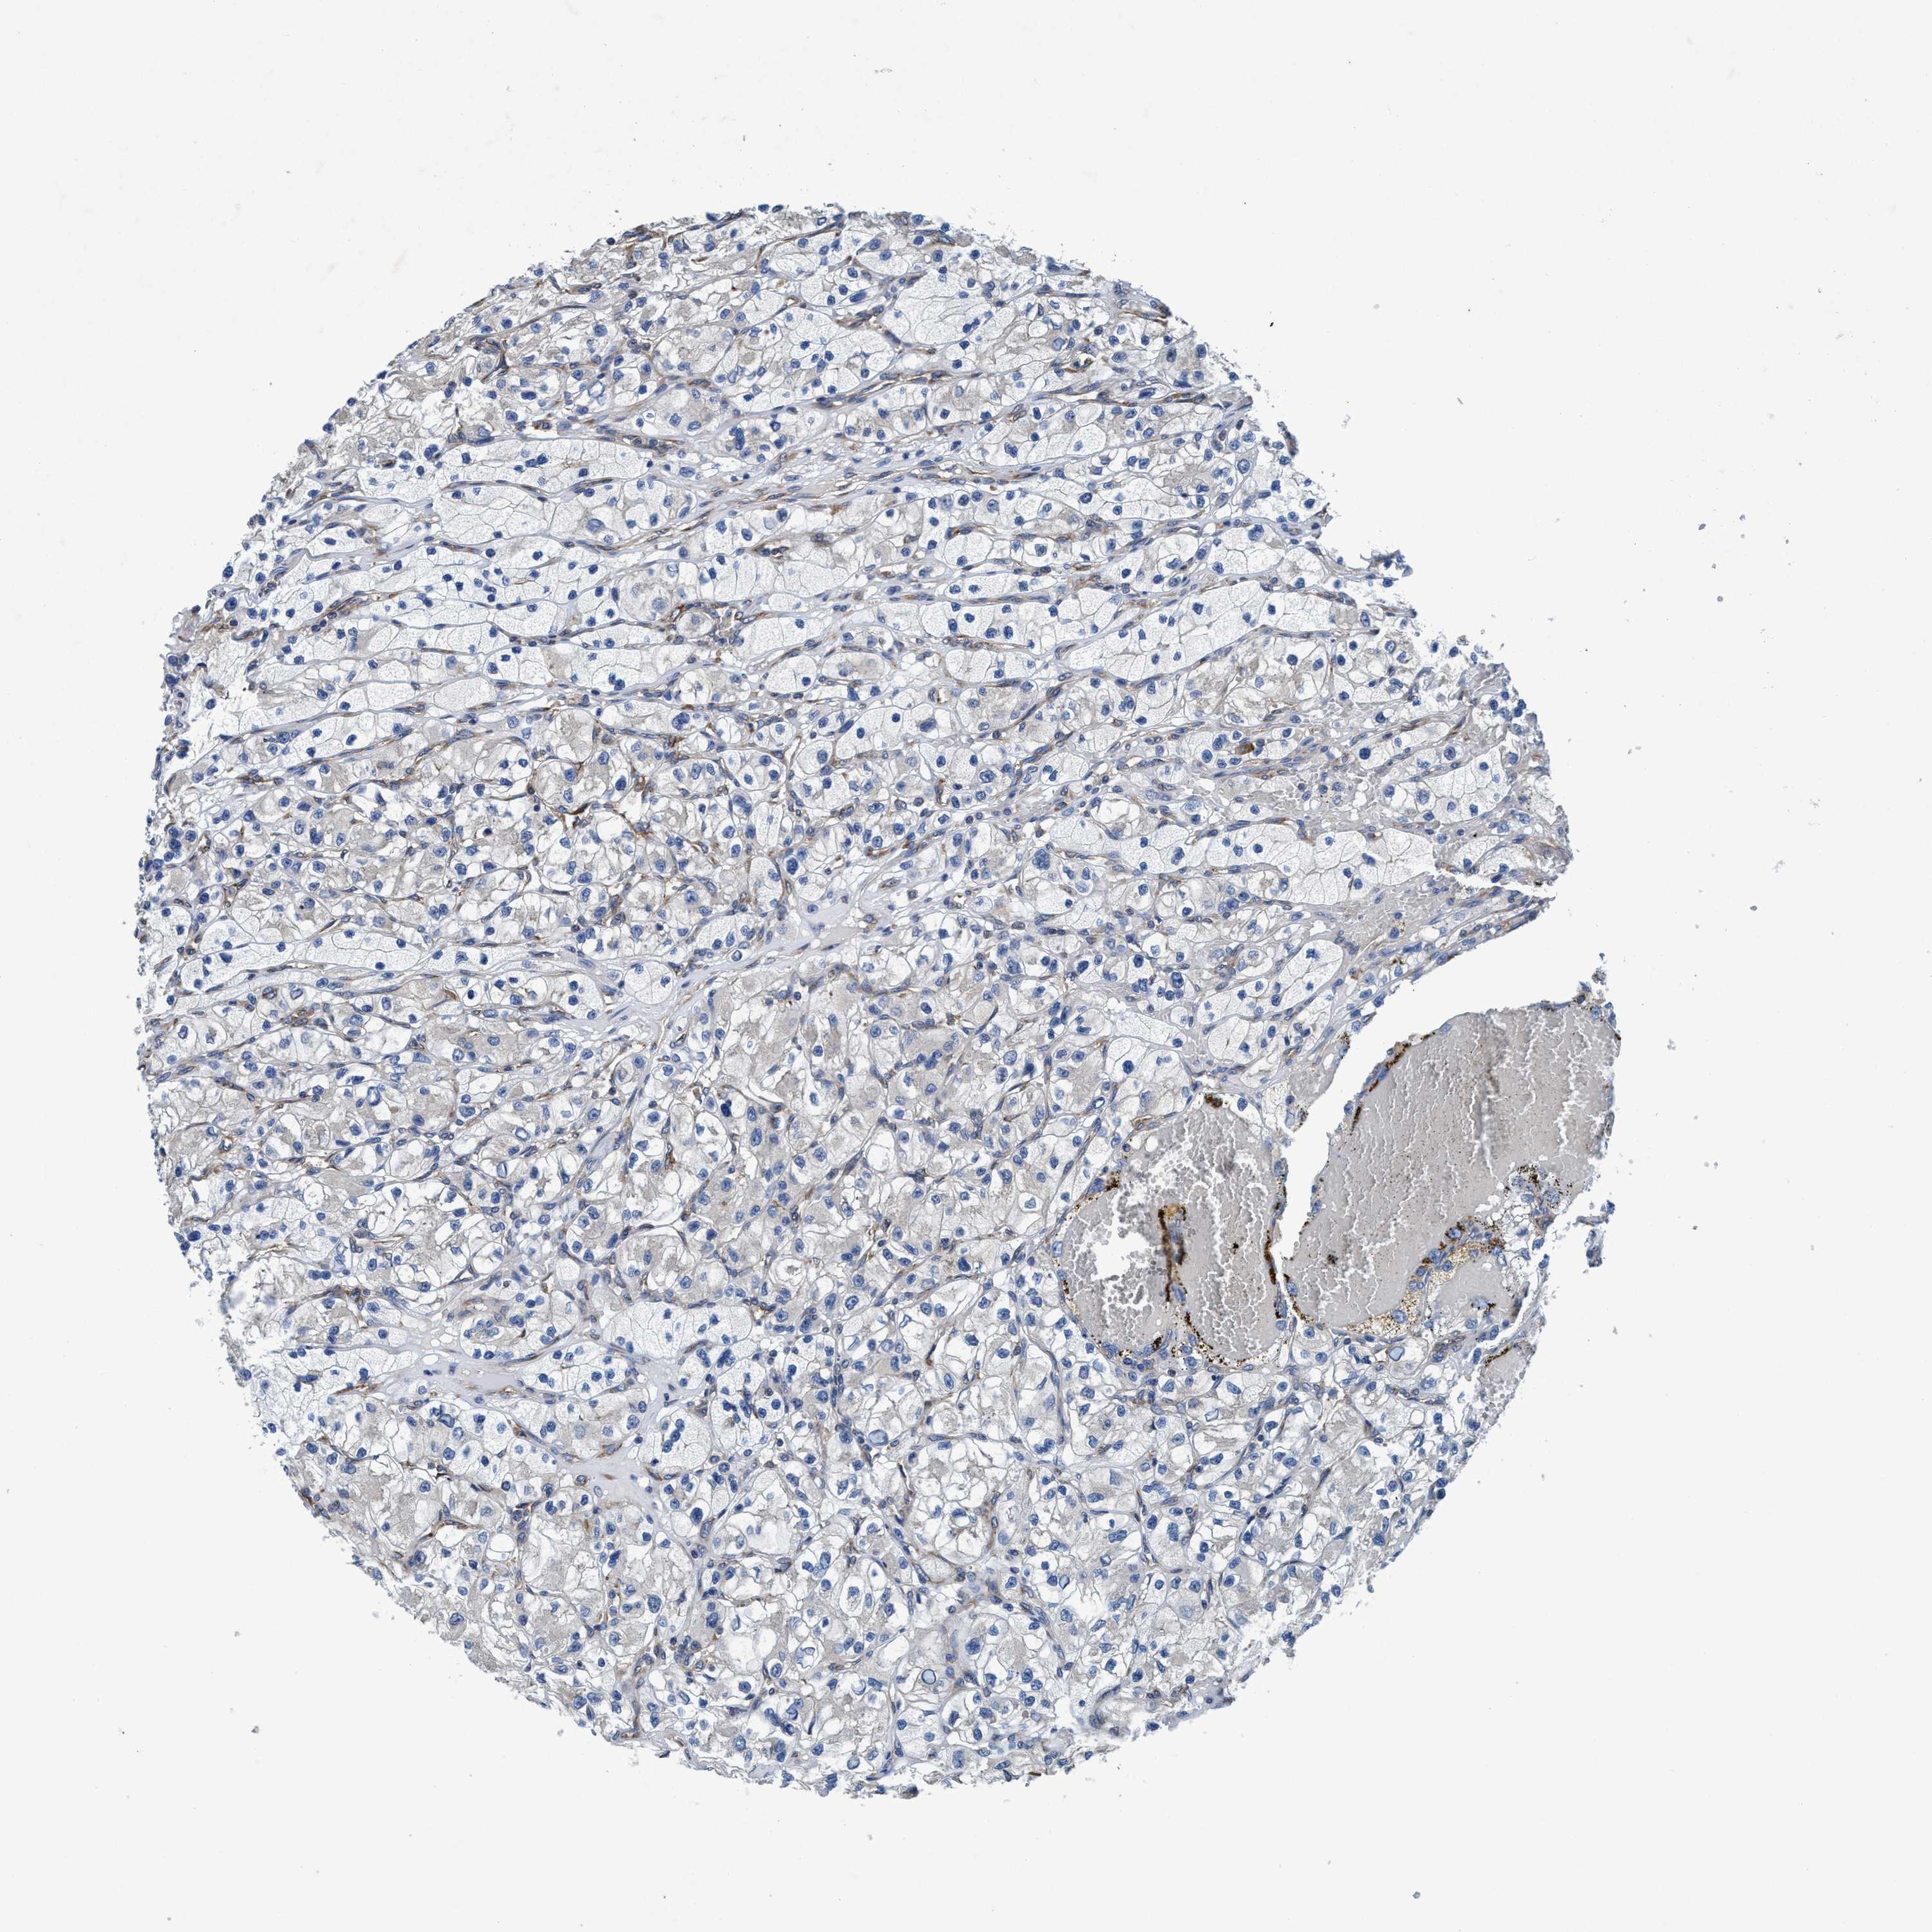

KIDNEY RENAL PAPILLARY CELL CARCINOMA (TCGA) - Interactive survival scatter ploti

The Survival Scatter plot shows the clinical status (i.e. dead or alive) for all individuals in the patient cohort, based on the same data that underlies the corresponding Kaplan-Meier plots. Patients that are alive at last time for follow-up are shown in blue and patients who have died during the study are shown in red.

The x-axis shows the expression levels (FPKM) of the investigated gene in the tumor tissue at the time of diagnosis. The y-axis shows the follow-up time after diagnosis (years). Both axes are complimented with kernel density curves demonstrating the data density over the axes. The top density plot shows the expression levels (FPKM) distribution among dead (red) and alive patients (blue). The right density plot shows the data density of the survived years of dead patients with high and low expression levels respectively, stratified using the cutoff indicated by the vertical dashed line through the Survival Scatter plot. This cutoff is automatically defined based on the FPKM cutoff that minimizes the p-score. The cutoff can be changed by dragging the vertical line or by entering a cutoff value in the square labeled "Current cut-off".

Under the Survival Scatter plot the p-score landscape (black curve; left axis) is shown together with dead median separation (red curve; right axis). Dead median separation is the difference in median mRNA expression between patients who have died with high and low expression, respectively. It is calculated as follows: median FPKM expression of dead patients with high expression - median FPKM expression of dead patients with low expression. This is intended to aid the user in visually exploring custom cutoffs and the associated p-scores and dead median separation.

Individual patient data is displayed and can be filtered by clicking on one or more of the category buttons on the top of the page. Categories describing expression level and patient information include: high, low, alive, dead, female, male and tumor stages. The scale of the x-axis can be toggled between linear and log-scale by clicking on the "x log" button. Mouse-over function shows TCGA ID, patient information and mRNA expression (FPKM) for each patient.

& Survival analysisi

Kaplan-Meier plots summarize results from analysis of correlation between mRNA expression level and patient survival. Patients were divided based on level of expression into one of the two groups "low" (under cut off) or "high" (over cut off). X-axis shows time for survival (years) and y-axis shows the probability of survival, where 1.0 corresponds to 100 percent.

ENDOG is potential prognostic, high expression is favorable in Kidney Renal Papillary Cell Carcinoma (TCGA)